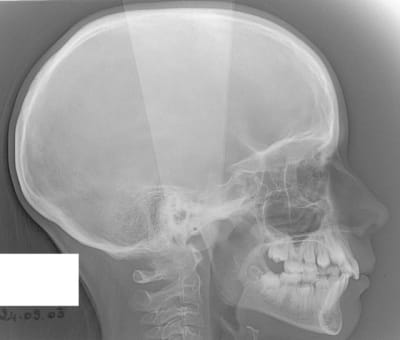

22/05/2008 à 00h10

début 2008,quadhélix en 0.28,pour vestibuler la 2,ce qui est fait

Tele2002 qhiepn - Eugenol

Tele2007 b6yul0 - Eugenol